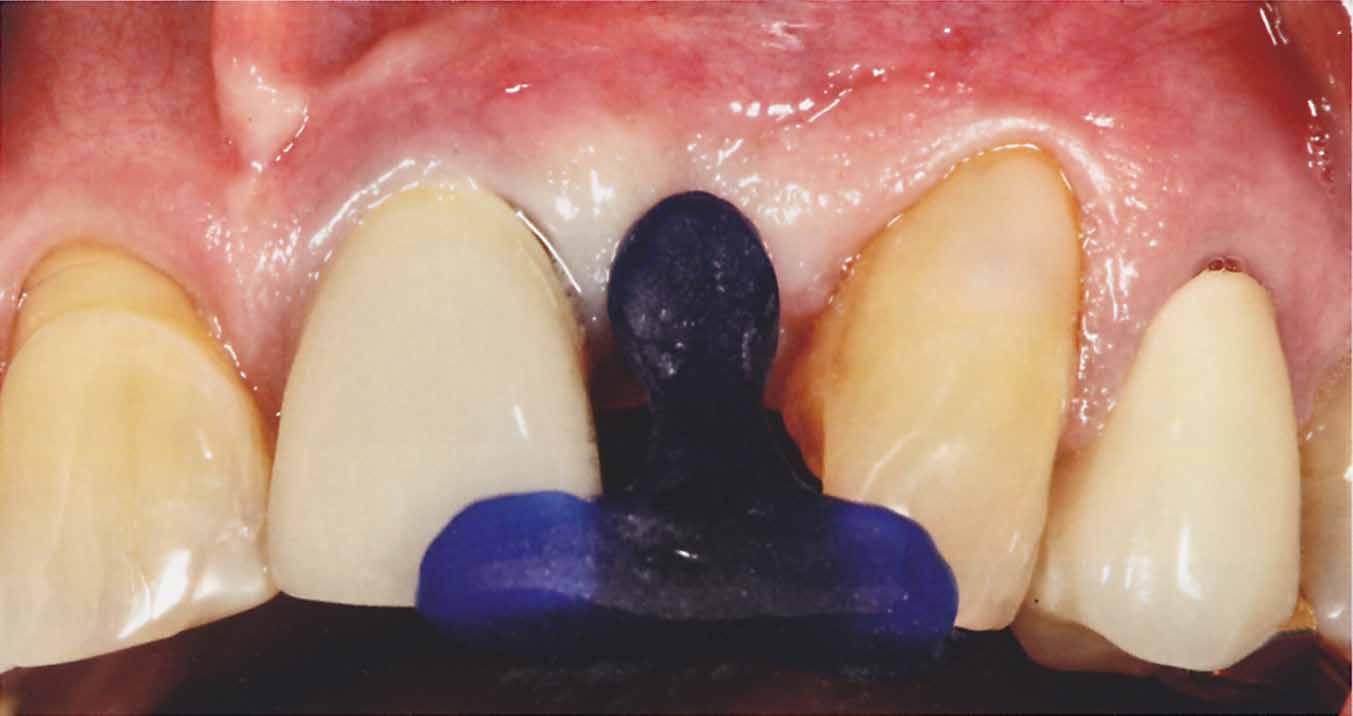

A 80 éves páciens 22-es fogának hiányát szerette volna megoldatni a rendelőben. Az implantációt költségessége miatt nem tudta vállalni. A 21-es fog már koronával volt ellátva, és kategórikusan elutasította ennek lengőtagos híddal való lecserélését, így egyértelmű volt a 23-as fogon való rögzítés szükségessége.

Mivel a szemfogak általában nagyon közel vannak az antagonistához, kettes pótlására a szárnyat inkább a nagymetszőre szoktuk tervezni. Ehhez persze invazív preparációra van szükség – érintetlen fogak esetén ez lehetőleg kerülendő.

A bemutatott esetben azonban könnyen döntöttünk, mivel a szemfog disztális részén nagy tömés volt. A defektust bevontuk az eset megoldásába.

A preparálást követően Provil-lal vettünk lenyomatot.

A laboratóriumban szekciós minta készült, blokk-stiftekkel (1. kép) , amelynek készítése során nagy figyelmet szenteltünk az ínymaszk (Majesthetik- Gingiimplant picodent) és a felfekvő lengőtag területének (2–6. képek)